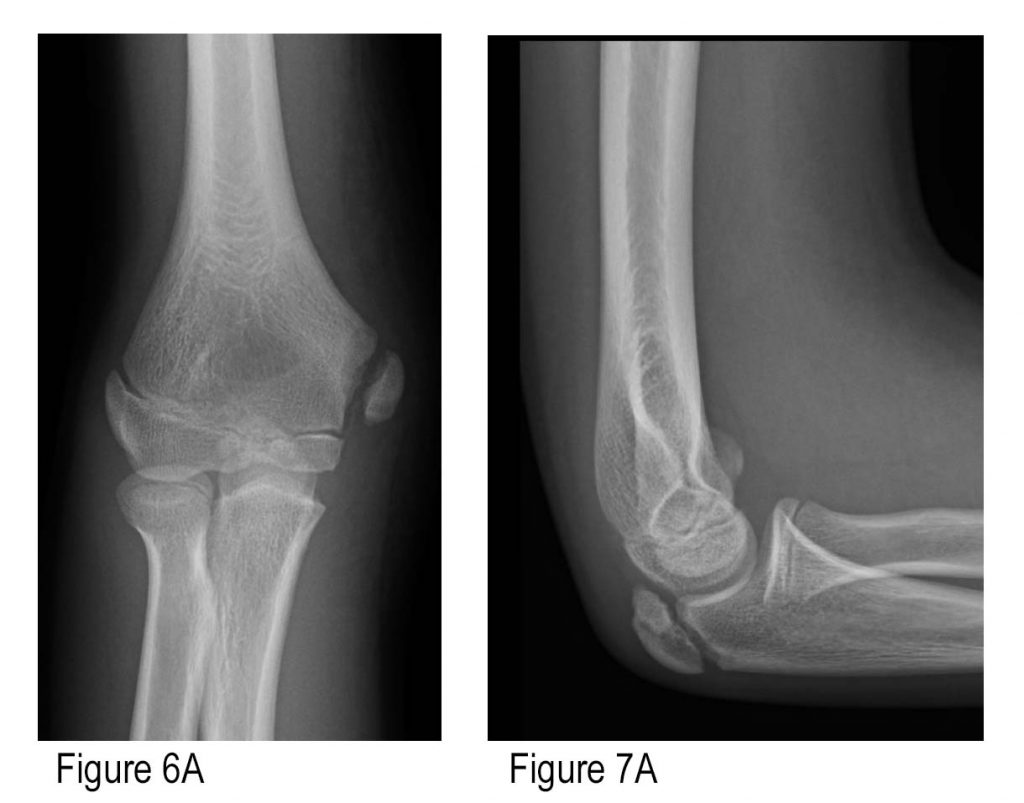

X Ray Elbow Normal

Normal elbow radiographs | Radiology Case | Radiopaedia.org Normal elbow x-ray - 7-year-old | Radiology Case | Radiopaedia.org Normal elbow series | Radiology Case | Radiopaedia.org File:X-ray of normal elbow by lateral projection.jpg - Wikimedia Commons | X Ray Elbow Normal